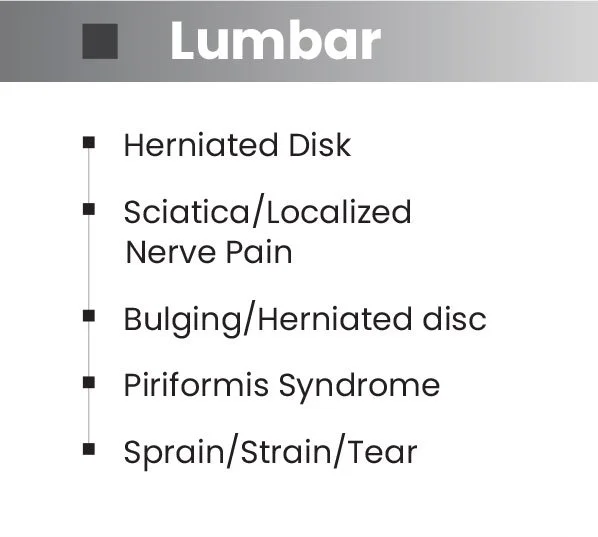

Effective Pain Reduction Across a Broad Range of Conditions.

Back, neck, shoulder, elbow and knee pain